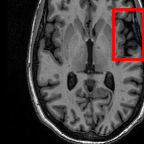

In practice, most MR volumes are taken anisotropically with a high resolution within slices and a sparse resolution between slices. For example, Fig. 1 shows a brain MR scan whose axial direction is sparsely sampled. As a result, image quality suffers when viewing from coronal and sagittal directions.

Figure 1: The axial, coronal, and sagittal views of an anisotropic MR volume are fitted to isotropic resolution through (Left) linear interpolation and (Right) our proposed slice-interpolation method.